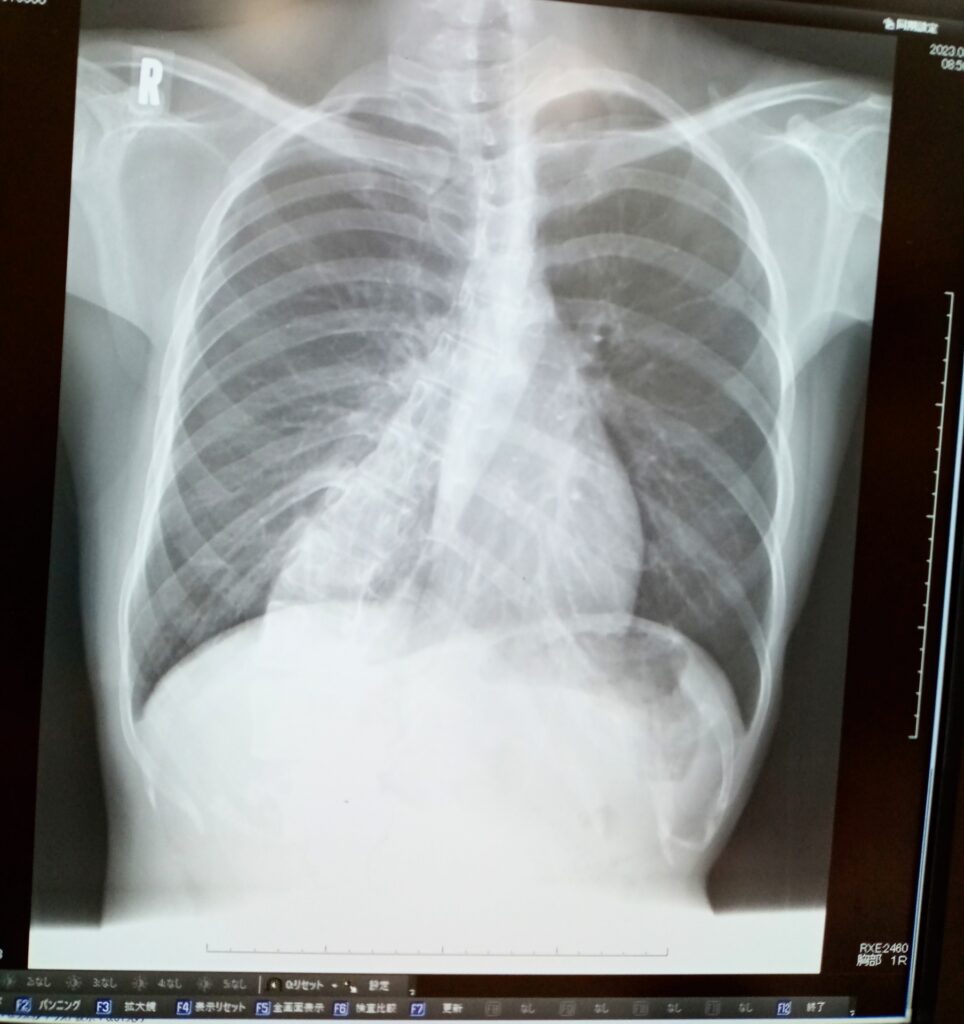

②単純X線像

カーブを判定し、側弯度はCobb(コブ)角で表記します。

これらの判定は側弯の程度を把握するために極めて重要になります。